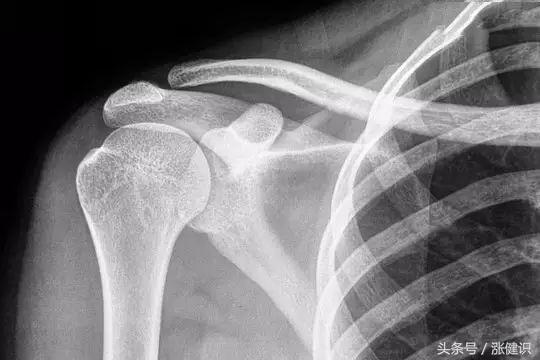

答案很明确,药物无法消除骨刺。骨质增生,俗称“长骨刺”。随着老年人免疫系统机能的逐渐降落,软骨的代谢功能、含水量也随之降落,关节的退变磨损会造成关节软骨损伤,从而继发关节周围的骨质增生。

说白了,骨刺就是增生的骨质,是关节软骨退化后多长出来的骨头,所以骨刺也是骨头。如果说有药物能溶解骨刺,那肯定也把旁边的骨头一起溶掉了。

了维持血液中钙浓度正常需要量,机体内部会自主进行调整,通过血液运输,从我们的骨骼及牙齿中,“借出”一些钙到血里维持血钙的平衡,弥补机体所需,这时我们会从X光片中看到骨质疏松的表现,但血中钙的含量往往正常。